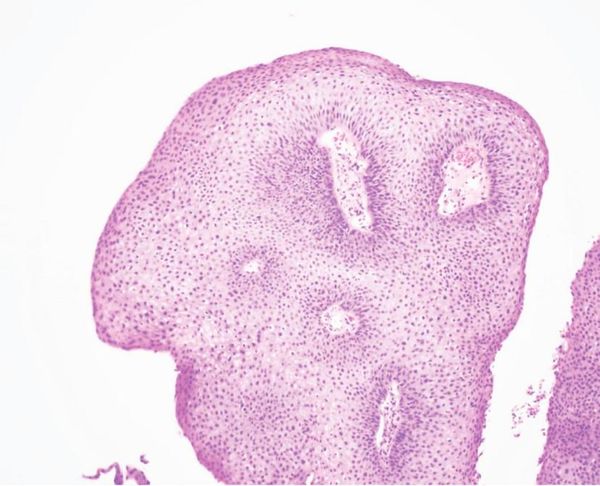

*题图来自网络,仅作示意用。

FDA于8月14日批准了Papzimeos(zopapogene imadenovec-drba),成为美国首个用于治疗复发性呼吸道乳头状瘤病(Recurrent Respiratory Papillomatosis,RRP)的疗法。申办方Precigen曾在2023年8月宣布获得FDA的同意将1/2期研究作为单个关键试验,利用人乳头瘤病毒(HPV)特异性免疫反应作为替代终点以支持加速批准。然而FDA走得更远,直接授予了完全批准。

RRP是一种罕见疾病,其特征是HPV诱导的气道乳头状瘤反复出现,患者通常需要多次手术。Papzimeos是一种基于非复制型腺病毒载体的免疫疗法,旨在刺激患者的免疫系统对抗病毒感染的细胞,从而控制疾病进程。此次批准基于一项单臂、开放标签的1/2期剂量递增加剂量扩展研究,评估了Papzimeos在过去12个月内接受过三次或以上手术的成人RRP患者中的安全性和有效性。

为什么单臂试验适用于RRP

RRP在美国大约影响27000名成年人,此前没有FDA批准的疗法。该疾病以复发性、快速生长的乳头状瘤为特征,需要频繁手术。由于手术后乳头状瘤的复发几乎是普遍现象,单臂研究允许与疾病已知的自然史进行有意义的比较,因为不复发(定义为在研究期间无需手术)可以可靠地归因于治疗效果。这类似于实体瘤试验,自发的肿瘤消退极为罕见,因此单臂研究一直是主要方法。